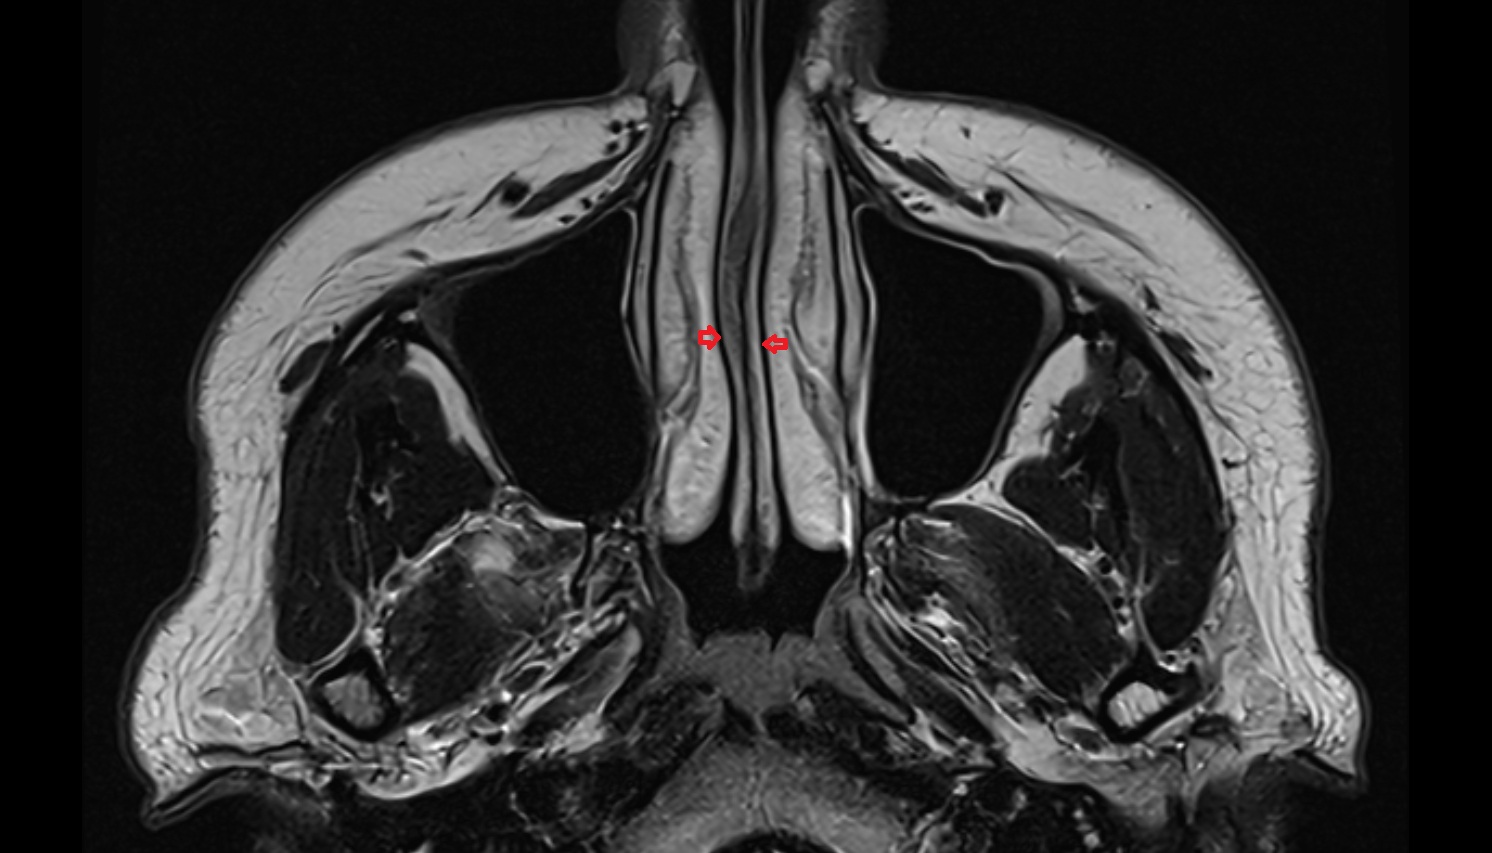

- Nasal septum